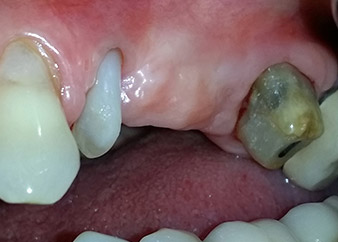

Después de la medicación tópica con un 25 % de gel de metronidazol (Elyzol) en las bolsas de la pieza 24, se inició un tratamiento causal de terapia periodontal con desinfección de toda la boca. El tratamiento ortógrado del canal radicular se revisó mediante una obturación con gutapercha termoplástica, un poste de fibra de vidrio y una acumulación de núcleo de composite (figura 2). El puente se recementó fuera de la oclusión para permitir la cicatrización sin problemas de los lugares de la GTR y la GBR.

Un mes después, en el día de la intervención, el dolor y la inflamación se habían reducido al mínimo en la pieza 24, pero seguía habiendo una movilidad de clase II de Miller. Después de la apertura de los colgajos y de la limpieza del tejido infectado periapical y perirradicular, la extensión del defecto óseo quedó evidente (figuras 2 y 3).

En la raíz bucal, faltaba todo el hueso vestibular y distal. Básicamente, la fijación se limitó a la raíz palatal, lo que corroboró el mal pronóstico preliminar. La pieza 27 también mostró una fijación horizontal reducida (figura 12) y una rarefacción apical mínima (figura 1), si bien sin síntomas clínicos.